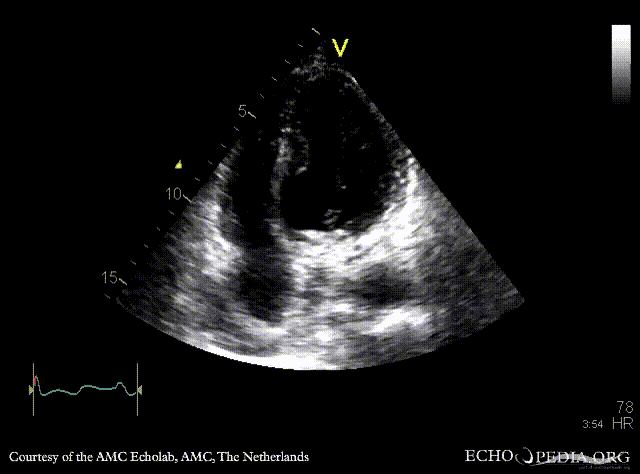

| A4CH: aneurysm of basal inferior wall | |